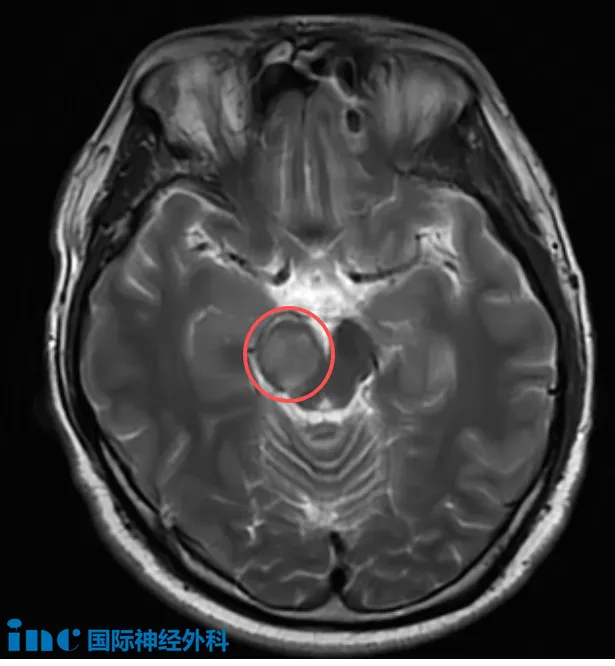

31岁的吴先生,正处于人生与事业的黄金阶段,却在2025年8月下旬因一次突如其来的头晕与耳闷,查出右侧中脑存在病变,自此与位于“生命中枢”的未知病变展开了较量。当地医院怀疑肿瘤可能性大,随后其症状在9月初消失,医生又建议观察。为寻求明确答案,一家人又奔赴北京,得到的回复是“考虑脑干胶质瘤,可以手术治疗”。

“可以手术”,本是一线希望,却将他们推入了更深的煎熬。因为从发现至今,吴先生看似与常人无异,仅有的异常只是偶尔袭来的困倦与哈欠。他们与所有脑干患者家庭一样,陷入那个最令人恐惧的假设:脑干手术风险巨大,如果手术后,情况变得更糟,该怎么办?

在抉择的关键时刻,他们找到巴特朗菲教授。此刻,他们想要知道:这位国际脑干大咖是否可以为他们进行这台“禁区”的手术?

“这并不是一个容易的手术,如果用1到10来衡量难度,我会给它大约7分。它不是最困难的手术,但确实比一般手术要复杂和苛求得多。关键在于,在尽量实现广泛切除的同时,保持患者的运动和感觉功能,实现切除与保护之间的平衡。这确实不容易,但我已在过去40多年中不断学习和实践,正是为了掌握如何做到这一点。我已经成功完成了非常多类似的手术,也正因为如此,我对这台手术充满信心!”这是巴教授深耕脑干多年的自信。